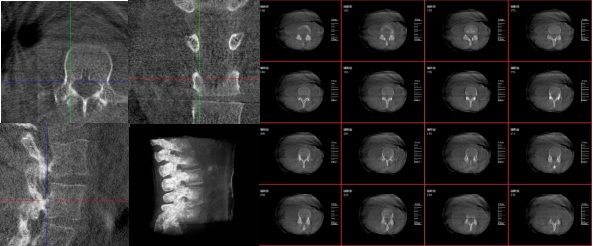

三维重建技术在医学影像诊断领域十分重要,它是一种利用计算机软件将二维医学影像(如X光、CT、MRI等)转化为三维立体图像的技术,可以为医生提供更直观、更清晰的图像信息,方便医生从多个角度观察病灶,从而更全面地了解病情,有助于提高诊断的准确性和效率。

6.可视化:将生成的三维模型以可视化的方式展示给医生,帮助他们更好地理解患者的病情。

3.手术导航:在手术过程中,医生可以通过三维重建技术实时观察手术器械的位置,提高手术的精确性和安全性。例如在关节外科手术中,存在植入物的错位在术中不易发现的情况,如果在术后CT中检查出,就不可避免地需要翻修手术,这就会增加并发症的概率以及感染风险。而通过术中三维影像设备PLX C7600的检查,可以立即发现植入物的错位,减少不必要的第二次手术。